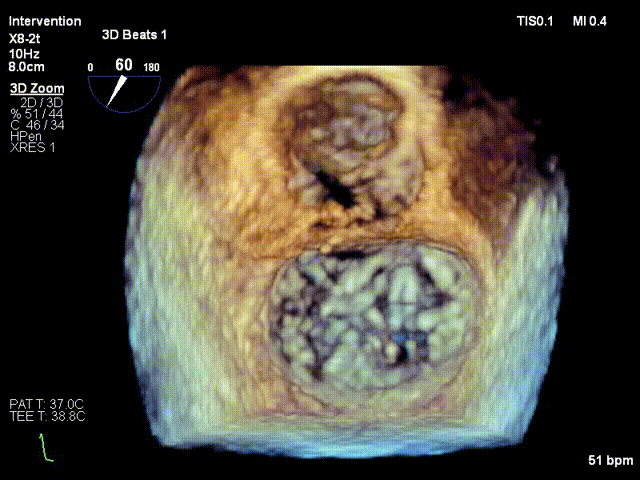

患者60岁男性,因胸痛主诉入院。术前食超显示患者DMR 4+,二尖瓣后叶P2偏P3脱垂、腱索断裂,脱垂宽度14.5mm,脱垂高度7.4mm,前叶长度33mm,后叶长度18mm,缩流颈宽度7.2mm,瓣口面积7.83cm²。

术前TEE影像